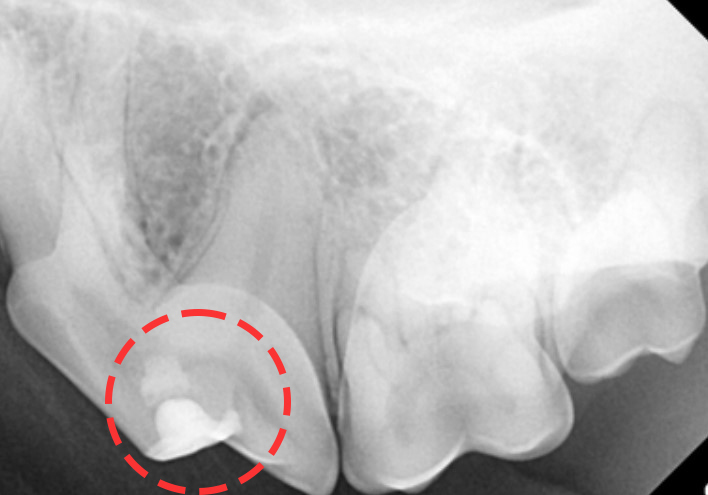

치료 적용이 가능한 상태인지를 정확하게 확인하기

위해 치과 엑스레이 촬영 후 스케일링을 진행했습니다.

계시고 치수 윗부분의 감염만 확인되었기에

치수 절단술 치료를 진행하였습니다.